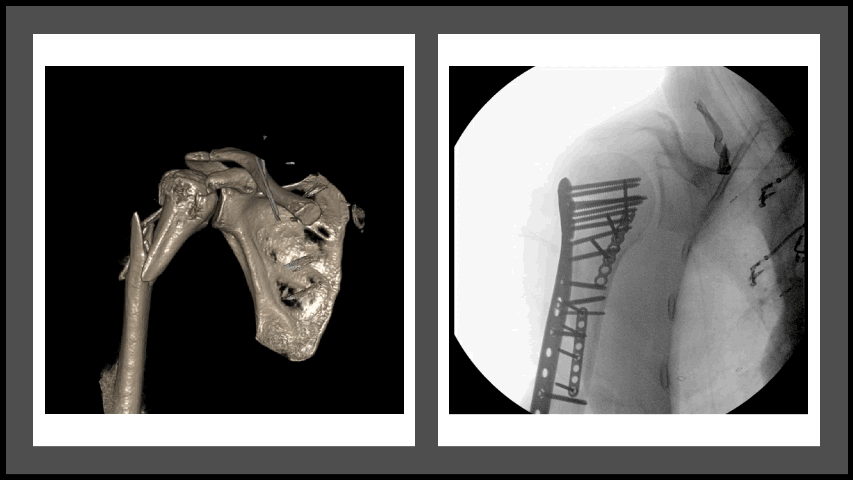

![]() Transverse patella fracture | ![]() Clavicle fracture | ![]() Glenoid and scapula fracture | ![]() Proximal humerus fracture |